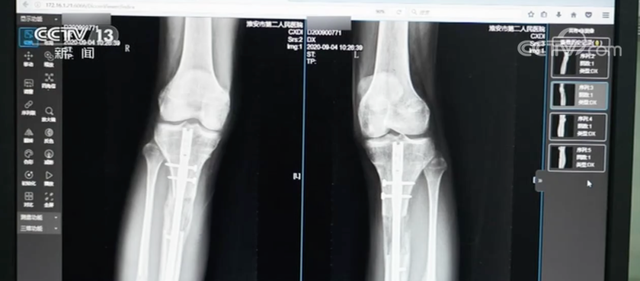

記者查詢發現,因為「斷骨增高手術」導致傷殘的案例並不在少數。

2022年,紅星新聞報道了一起「斷骨增高致不能行走」的新聞。江西南昌一名19歲的女生原本身高154cm,做了脛腓骨延長手術後,雖然增高了6公分,但出現行走障礙。經檢查,她的膝關節與踝關節都已經僵硬,不能完全靠自己站起來,需要依靠拐杖輔助行走。

圖源:央視新聞

「斷骨增高手術」又稱「肢體延長術」。它是根據肢體組織在一定的力量刺激下可以再生的原理,把小腿或大腿的骨頭「斷開」,然後在體外安裝具有牽伸作用的外固定支架,以每天不超過1毫米的速度,將肢體緩慢延長到滿意的長度。

此外,「斷骨增高手術」還具有多方面的危害。有骨科醫生表示,在實施「斷骨增高手術」時,外固定「增高器」的鋼針要穿透患者的雙腿,可能損傷腿部的血管、神經組織,造成感染,甚至引發骨髓炎,造成殘疾。同時,「斷骨增高手術」會造成血管損傷,嚴重的腿部血液供應障礙可能造成下肢組織壞死。